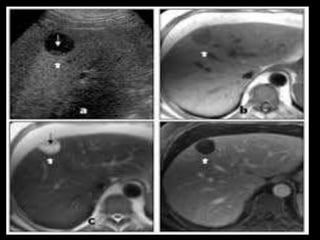

HEMANGIOMA HEPATICO

• MUJERES MAS FRECUENTE

• HALLAZGOS:

– MASA HIPODENSA

– HIPERCAPTACIÒN DEL CONTRASTE 20 A 30

MINUTOS

– TRAS LA ADMINISTTRACIÒN RAPIDA DE

CONTRASTE APARECEN AREAS

NODULATRES HIPERCAPTANTES